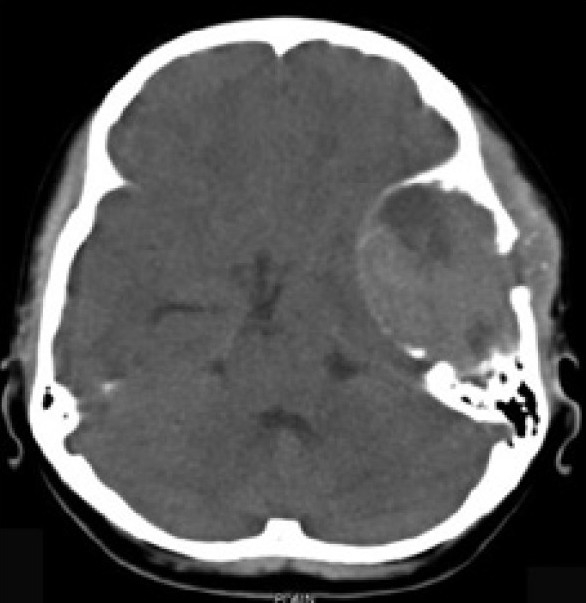

The Computed Tomography Scan (CT Scan) of the brain showed a rounded, well-defined, heterogeneously hyperdense, enhancing lesion in the left temporoparietal region, with a mass effect and destruction of the left temporal bone, extending into the scalp, suggesting the possibility of a meningioma. No evidence of calcification was noted within the lesion [Figure 1]. Magnetic resonance imaging (MRI) of the brain showed a left temporal lesion, hypointense on T1, heterointense on T2, with heterogeneous enhancement [Figure 2]. The lesion measured 6.0×4.6×7.4 cm. A significant mass effect was detected with a midline shift to the right, of 15 mm. The diffusion weighted image showed mild restriction. Magnetic resonance spectroscopy showed choline and N-Acetyl Acetate peaks.

| Fig. 1 Preoperative CT scan of the brain showed a rounded, well-defined, heterogeneously hyperdense, enhancing lesion in the left temporoparietal region, with a mass effect and destruction of the left temporal bone extending into the scalp, suggesting the possibility of meningioma. No evidence of calcification was noted within the lesion